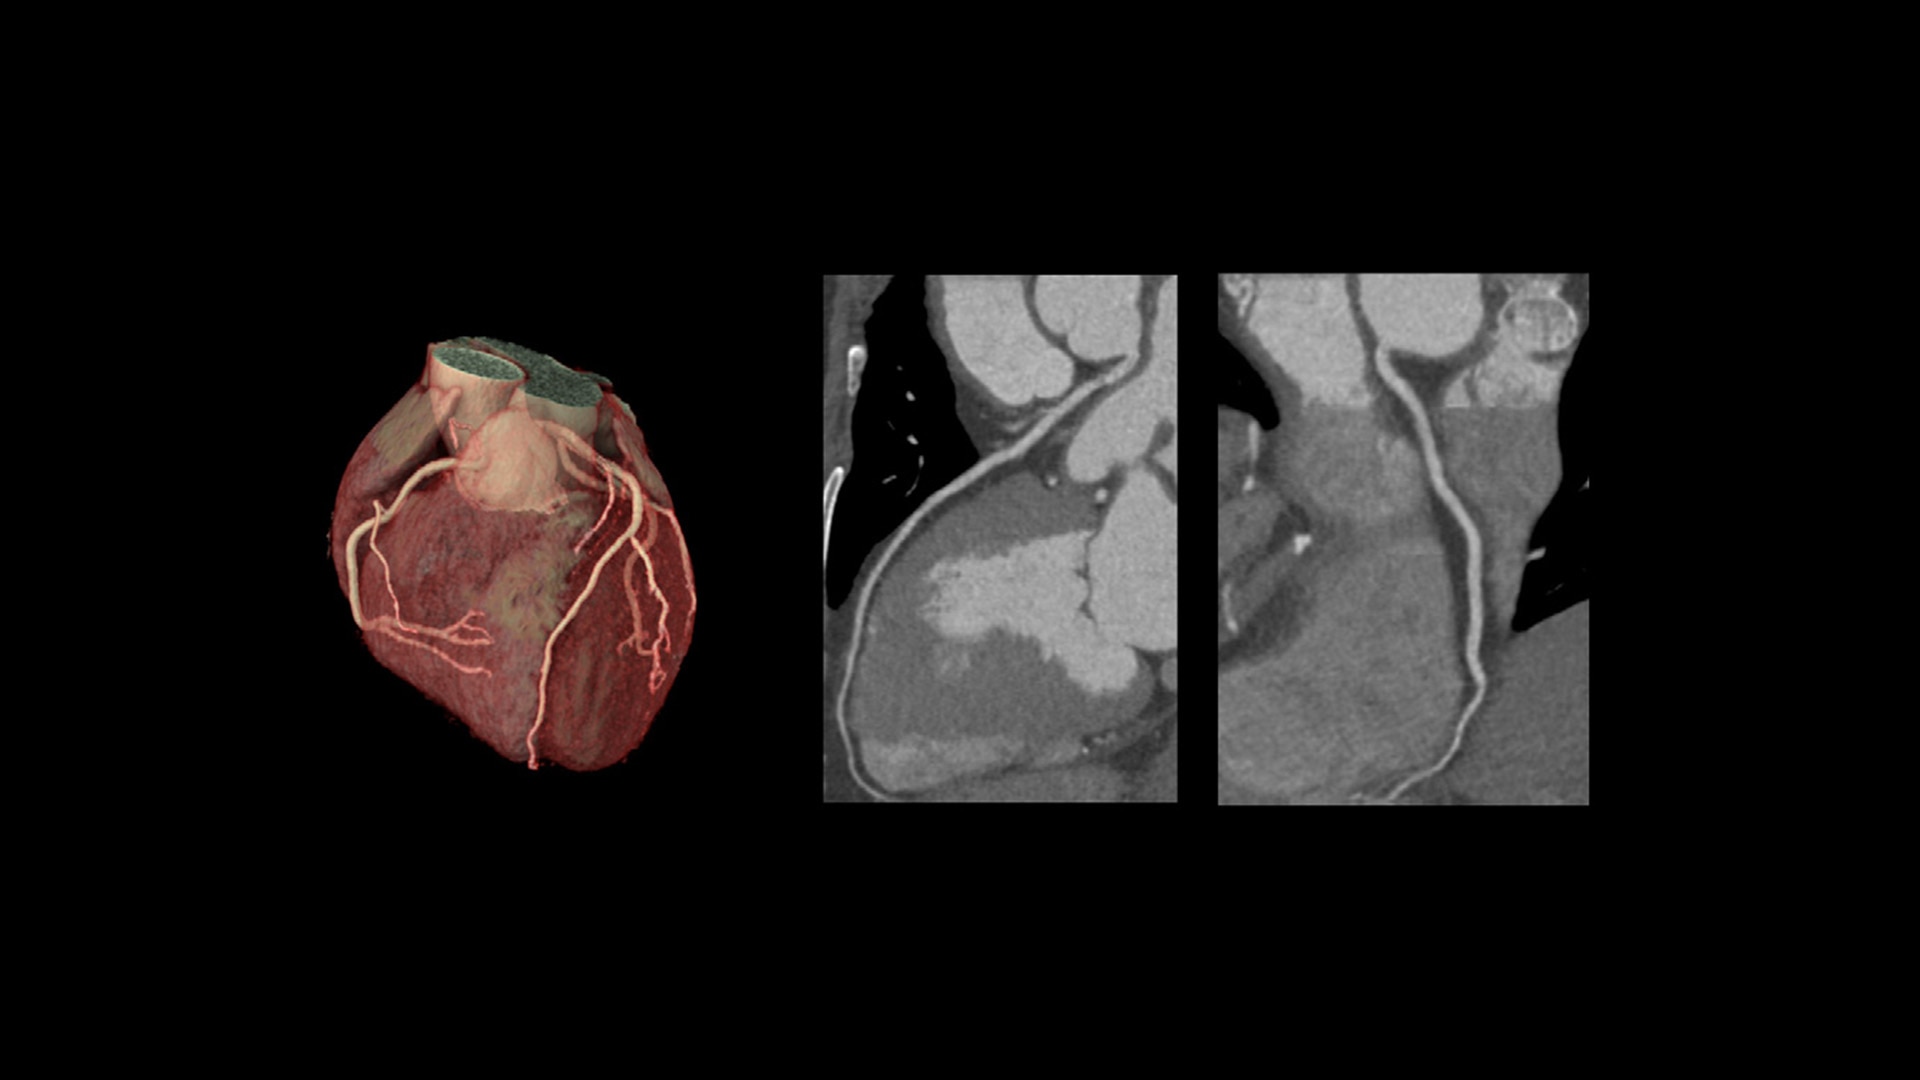

TrueFidelity DL + True Enhance DL

Better together

With the Revolution Ascend Platform, you can combine both of our AI-based imaging reconstruction technologies to create one stunning image. By combining True Enhance DL with TrueFidelity DL, you can achieve images that have less noise, enhanced sharpness and better noise texture than images obtained with ASiR-V.

TrueFidelity DL

Deep learning for a deeper understanding

TrueFidelity™ DL is our state-of-the-art image reconstruction technology that uses a DNN to generate high-definition, low-noise CT images. It produces images with exceptional sharpness, low-contrast image quality performance and your preferred noise texture, at the same dose.¹